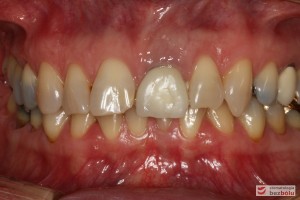

Do naszej placówki zgłosiła się starannie planująca swoje działania Europejka, mieszkająca na stałe w Kotlinie Jeleniogórskiej. Jej oczekiwania dotyczyły bardzo metodycznie zaplanowanego planu leczenia. Celem jaki postawiła przed naszym zespołem lekarzy było wyeliminowanie wszystkich wątpliwych i nierokujących wypełnień, a także poprawa estetyki w zakresie lewego siekacza centralnego w szczęce. Został rozpisany blisko dwuletni plan wymiany zużytych i nieszczelnych wypełnień amalgamatowych i kompozytowych. Zaplanowano również przygotowanie endodontyczne wybranych zębów w szczęce i żuchwie, a także zaopatrzenie w inlay’e porcelanowe i korony ceramiczne wykonane w systemie e-max.